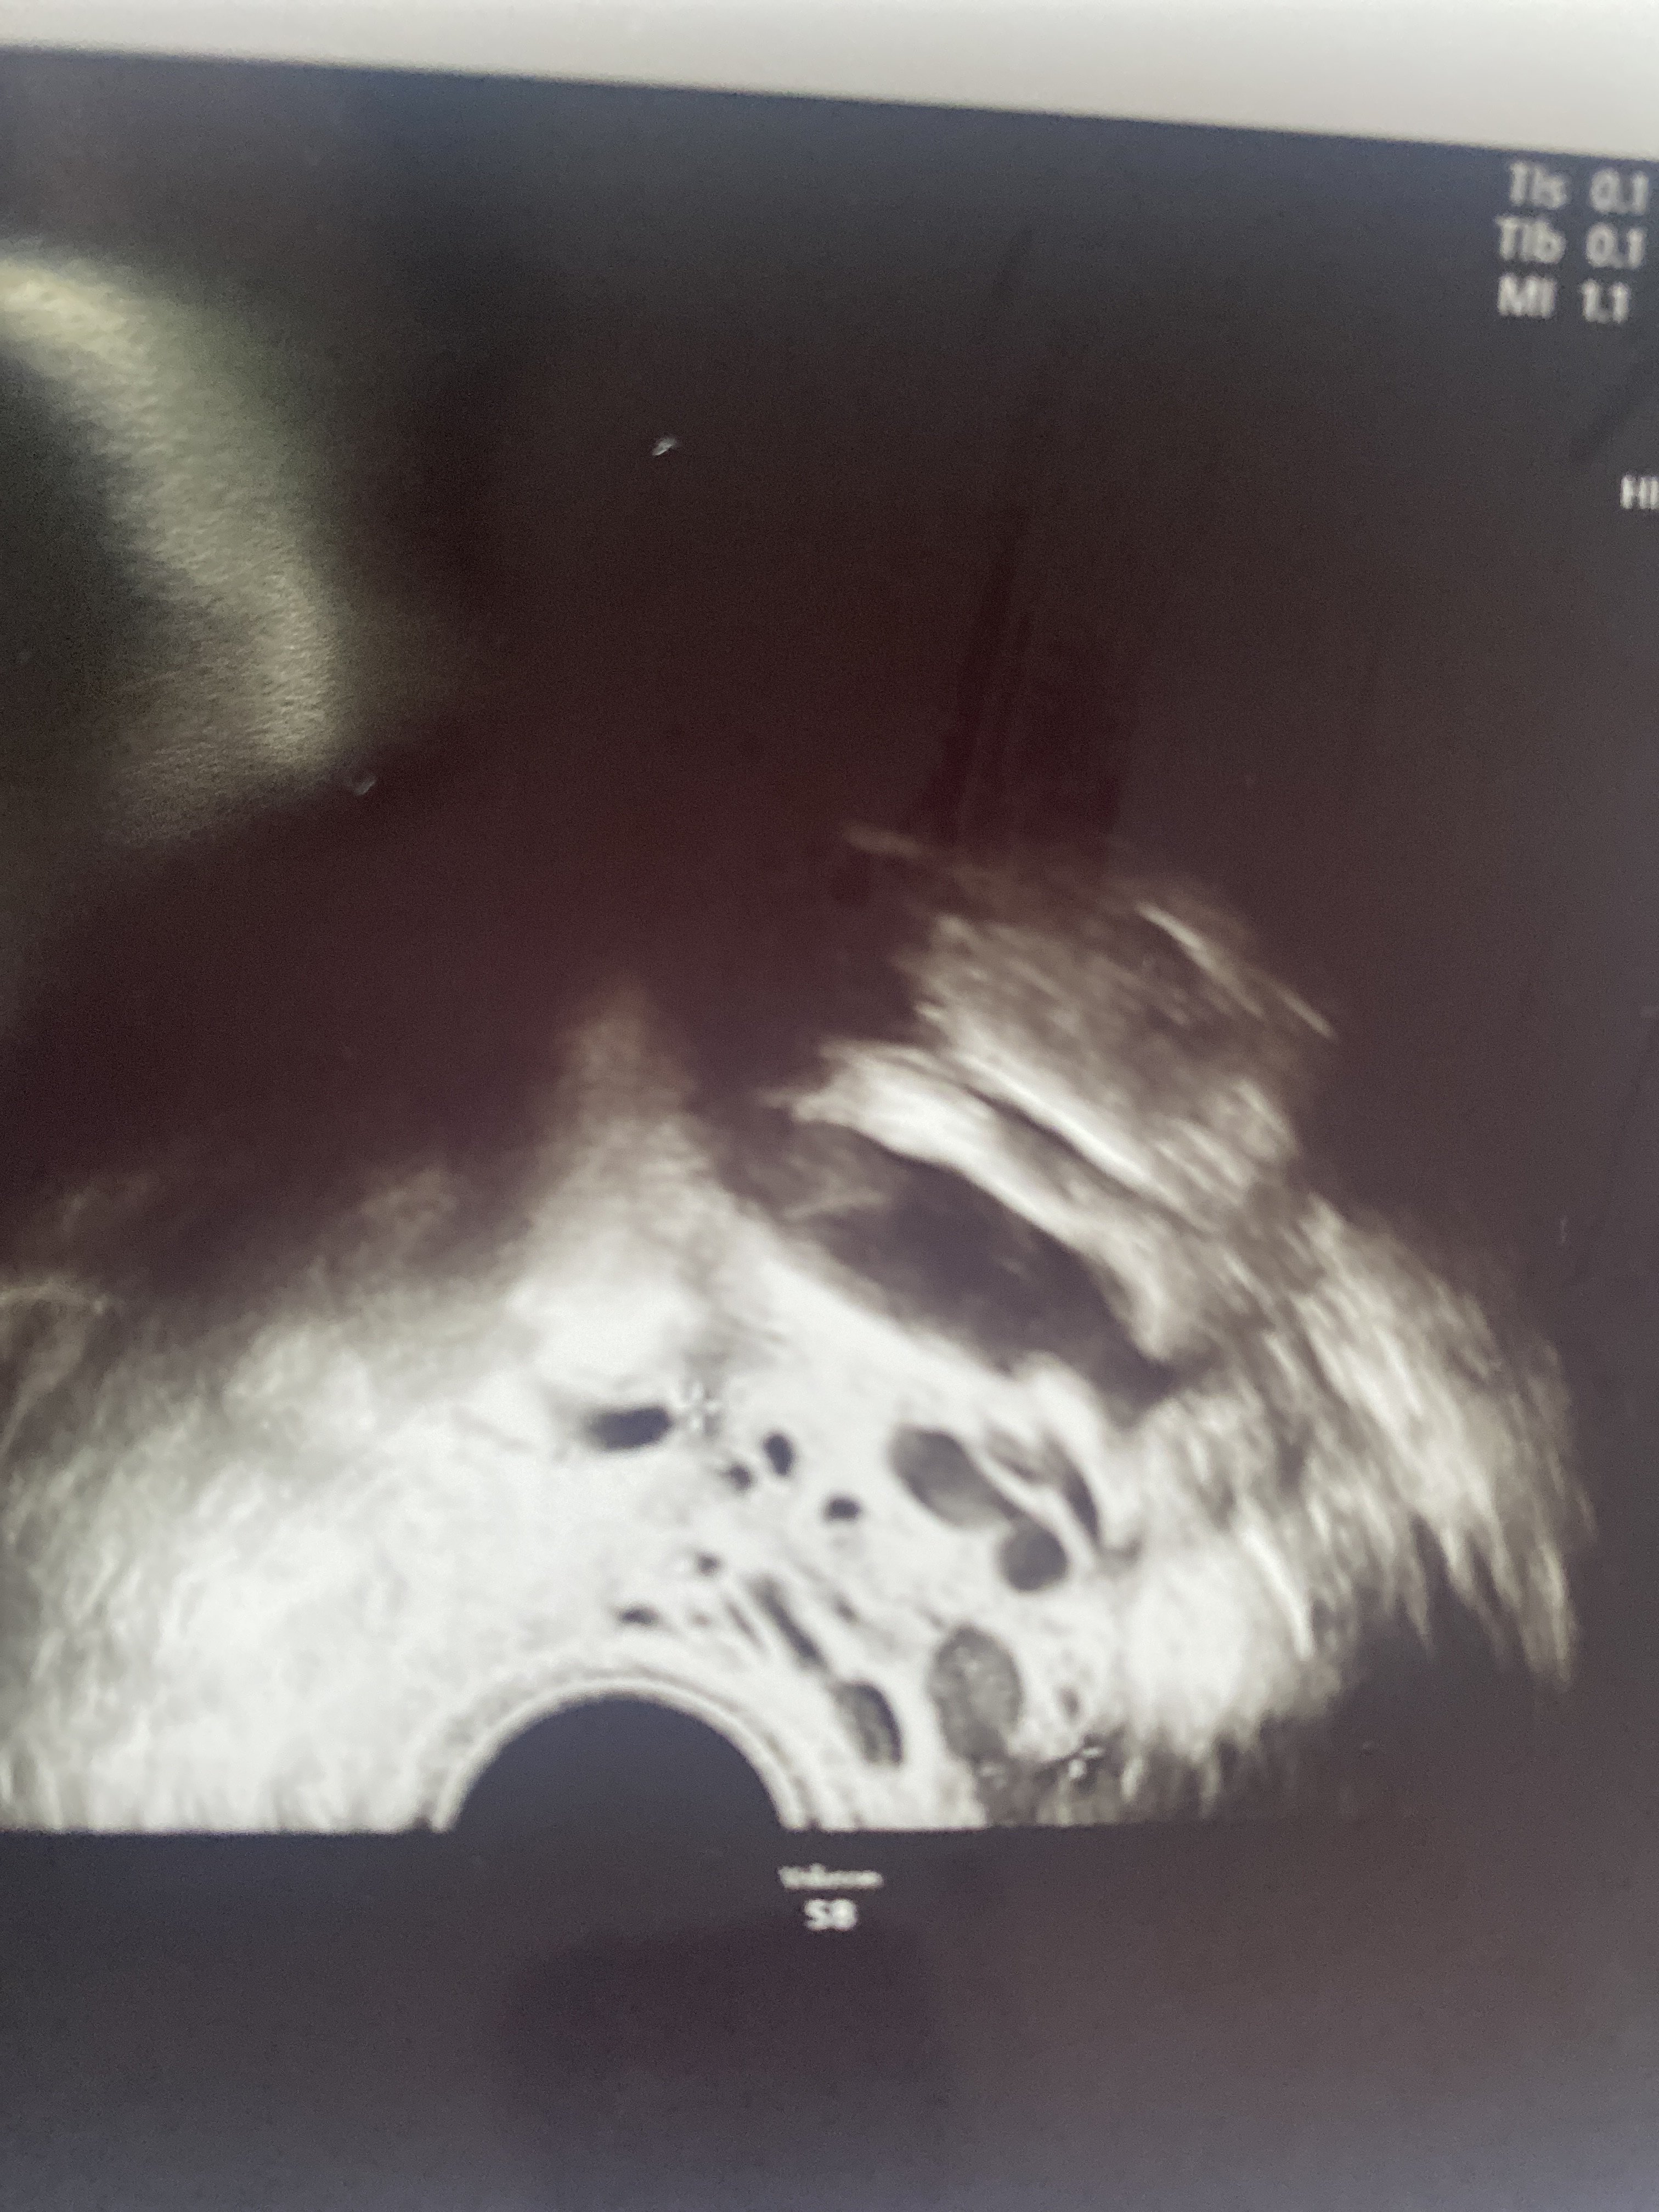

Nie mam pojęcia które zdjęcie jest czego, nie tłumaczył a ja nie pytałam, nie miałam siły na to

Załączniki

• image.jpg

image.jpg

1,9 MB · Wyświetleń: 94

1,6 MB · Wyświetleń: 96

1,7 MB · Wyświetleń: 96

Prawdopodobnie tak

Zaraz wam wstawię zdjęcia z usg i faktycznie w poprzedniej ciąży przy podobnej becie pęcherzyk był o wiele większy.

Ginekolog przekazał mi że mam coś w lewym jajniku ale nie jest w stanie mi powiedzieć czy to nie jest drugi pęcherzyk bo beta jest podejrzanie wysoka patrząc na ten co jest ulokowany w macicy i dostałam skierowanie do szpitala z ciążą pozamaciczną.

Próbowałam umówić się jeszcze na dzisiaj do mojej ginekolozki ale dzisiaj nie przyjmuje :(

Nie wiem kompletnie co robić, niby drugi lekarz mówi o pozamacicznej ale żadnej mi tego nie potwierdził. Zrobiłam znowu betę dzisiaj to porównam sobie wynik z wczorajszą i najwyżej wieczorem pojadę do szpitala lub jutro z rana…